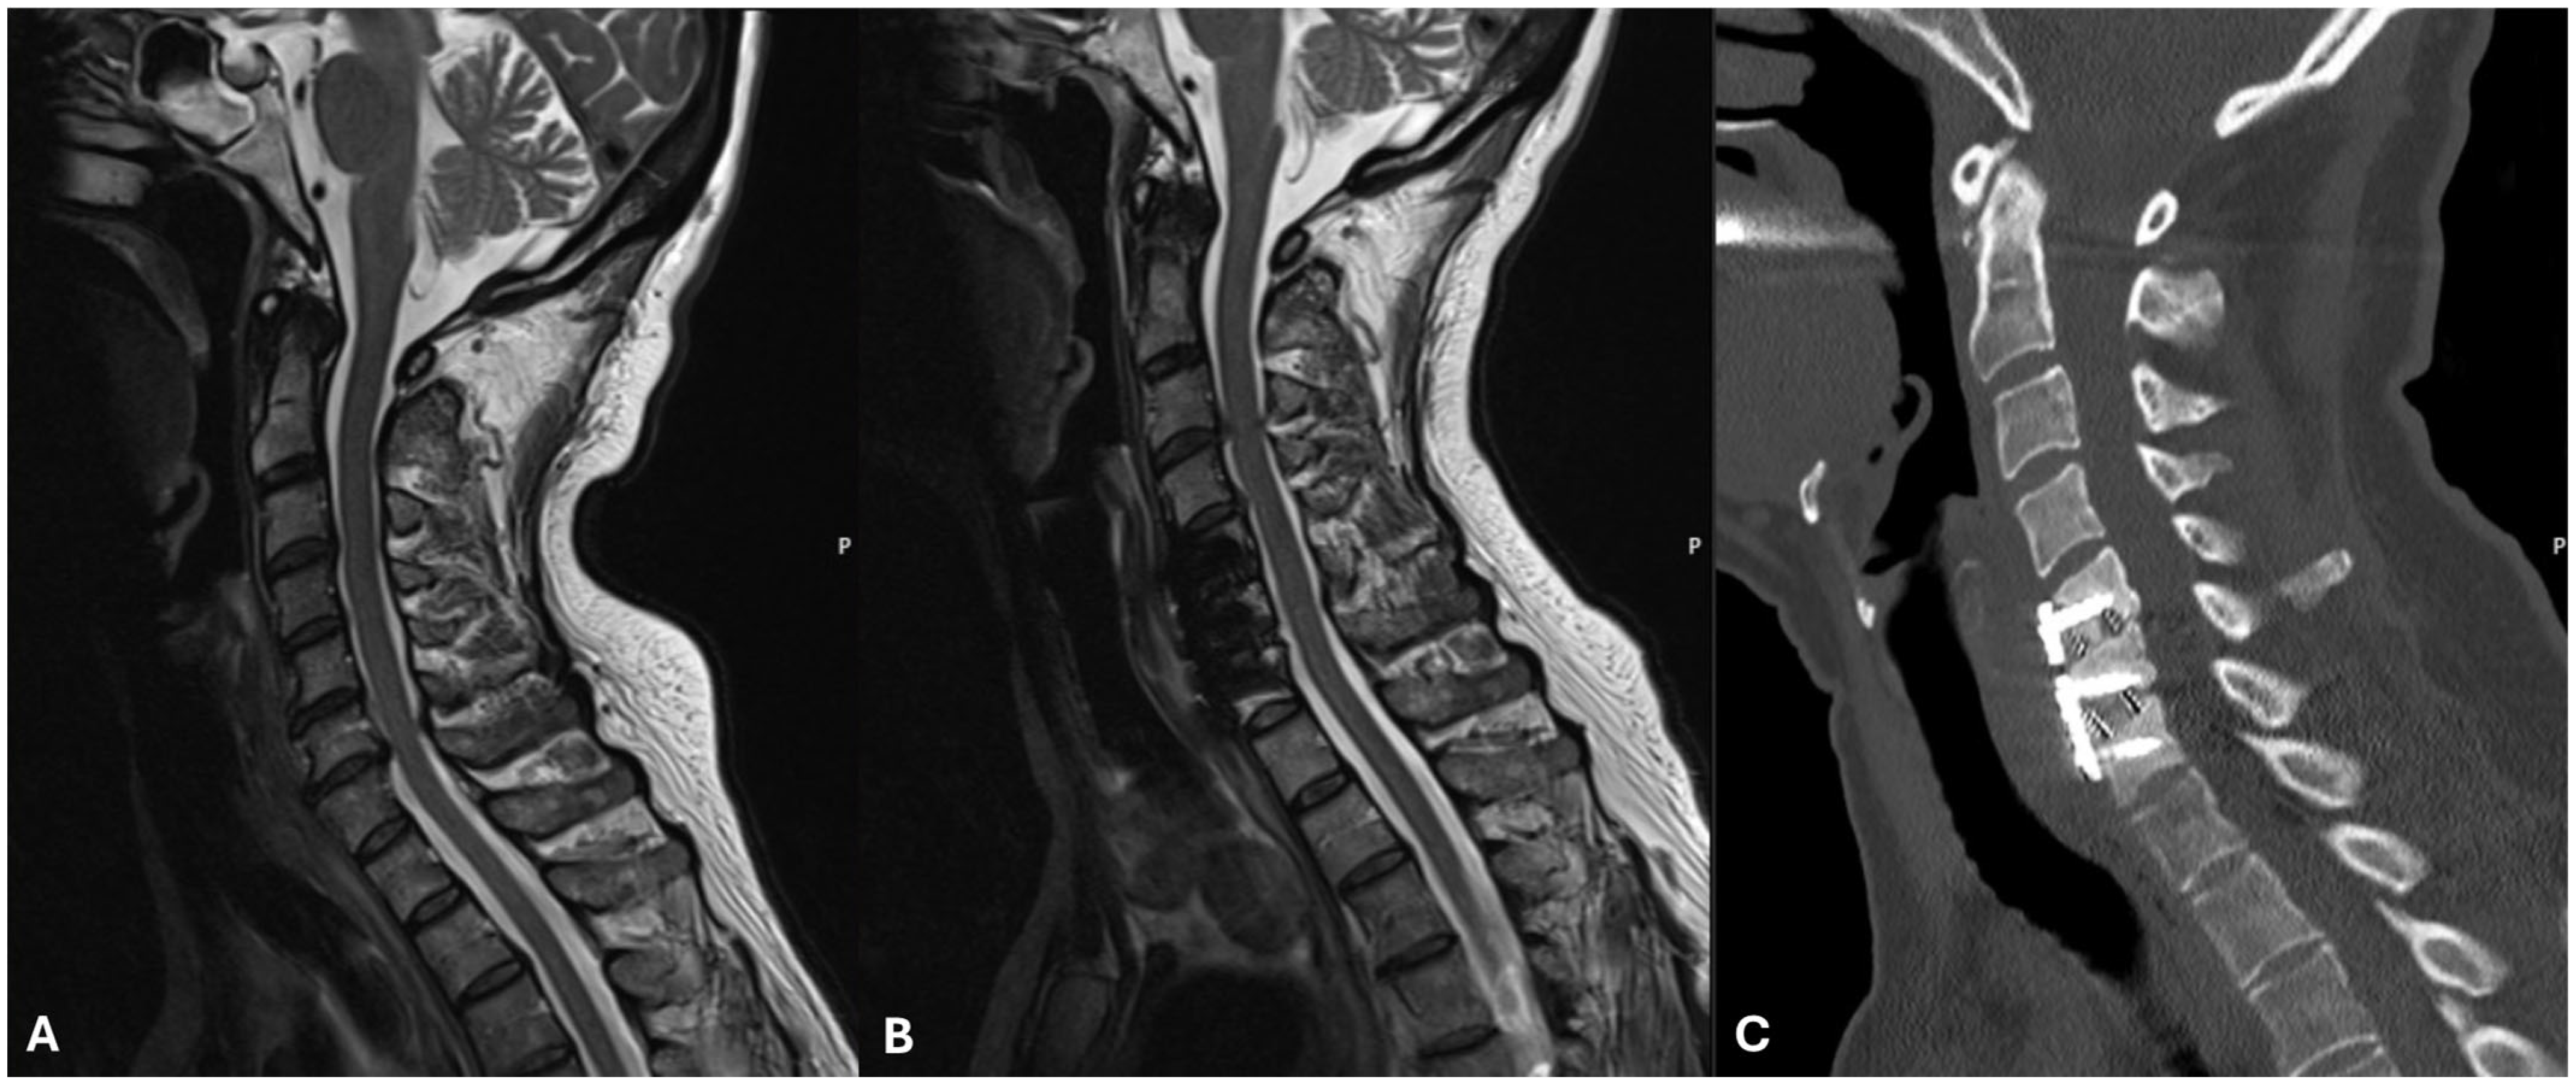

3.1.1. Case 1

| 2023 Hellquist et al. Sweden | Current case report | 1 | Radiculopathy | ACDF | C5–C7 | Temporary | Hoarseness Tongue deviation | 2, 4, 5 months | Possibly mechanical injury from the endotracheal tube | NA |

| 2023 Hellquist et al. Sweden | Current case report | 1 | Radiculopathy | ACDF | C5–C6 | Temporary | Hoarseness Dysarthria Dysphagia Tongue deviation | 2 months | Unclear, possibly mechanical injury from the endotracheal tube | Speech and swallowing therapy |